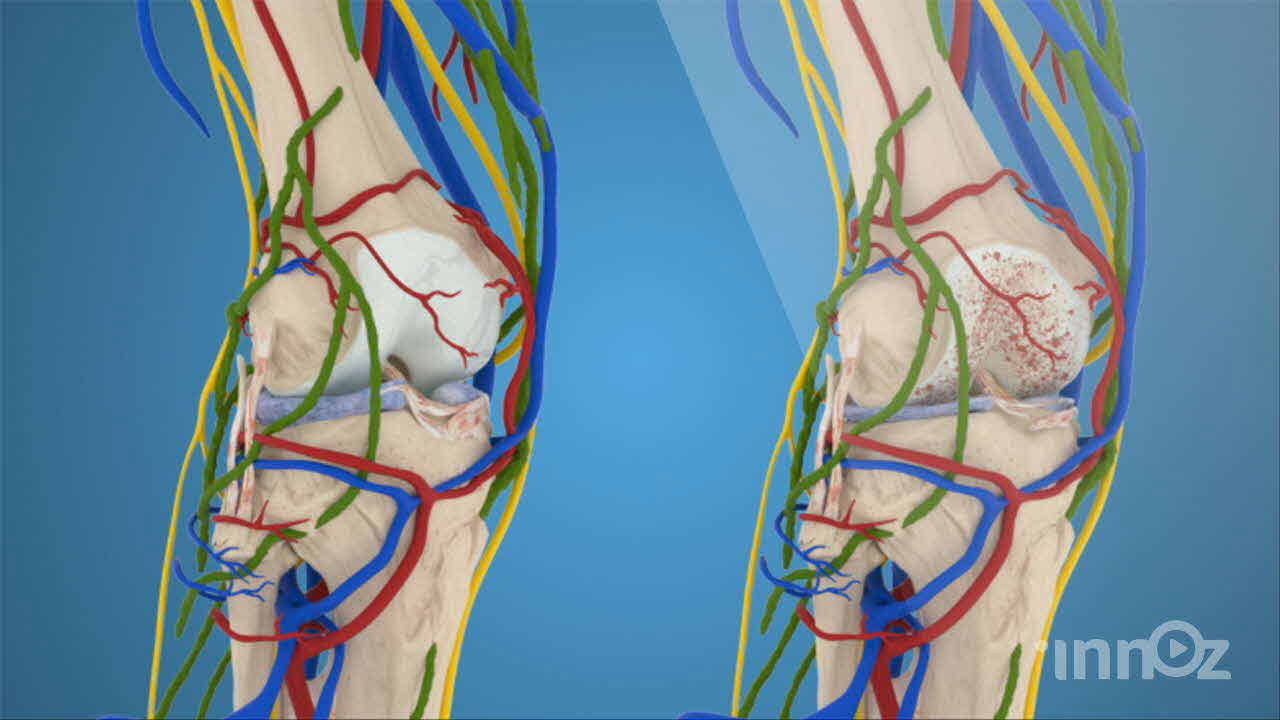

2020 파마리서치프로덕트 무릎관절손상 영상제작

파마리서치